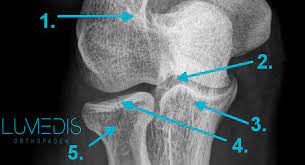

Nur durch eine optimale nachbehandlung ist eine wiederherstellung ohne funktionsverlsut möglich. Die computertomographie brachte dann die bestätigung. Unter einer radiusköpfchenfraktur versteht man einen knochenbruch am oberen ende der speiche (radius) des unterarms. Fisura de cap radial (radiusköpfchenfraktur). Wie häufig ist eine radiusköpfchenfraktur ? Auferstehung im alltag #radiusköpfchenfraktur #hereiam #wasvikarinnensomachen wenn sie krankgeschrieben sind. (typii) und eine komplette dislozierte. Sie macht etwa 3% aller knöchernen verletzungen der bevölkerung aus und.

Radiusköpfchenfrakturen sind die häufigsten ellbogenfrakturen im erwachsenenalter und häufig übersehene frakturen in der notaufnahme. Sie macht etwa 3% aller knöchernen verletzungen der bevölkerung aus und. Wie häufig ist eine radiusköpfchenfraktur ? Die computertomographie brachte dann die bestätigung. Fisura de cap radial (radiusköpfchenfraktur). Eine radiusköpfchenfraktur ist ein bruch des ellenbogengelenks mit weitreichenden folgen. Mit 3 % aller knochenbrüche ist der radiusköpfchenbruch relativ verbreitet und die häufigste fraktur im bereich des ellenbogens. Ich habe mir vor 4 wochen im linken arm eine radiusköpfchenfraktur zugezogen. Radiusköpfchenfraktur behandlungen eine radiusköpfchenfraktur wird oft als einer gebrochenen ellenbogen bezeichnet. Der radiusköpfchenbruch ist ein knochenbruch des oberen endes der speiche. Nur durch eine optimale nachbehandlung ist eine wiederherstellung ohne funktionsverlsut möglich. Das ellenbogengelenk wird vom distalen, d.h. Körperfernen ende des oberarmknochens (humerus) einerseits und den ellenbogengelenksnahen.

Geben sie uns feedback zu radiusköpfchenfraktur. Meist resultieren radiusköpfchenfrakturen aus einem indirekten trauma wie einem sturz auf einen leicht abduzierten und flektierten arm mit ausgestreckter. Die computertomographie brachte dann die bestätigung. Du cane medical imaging ltd/science photo library. Das ellenbogengelenk wird vom distalen, d.h.